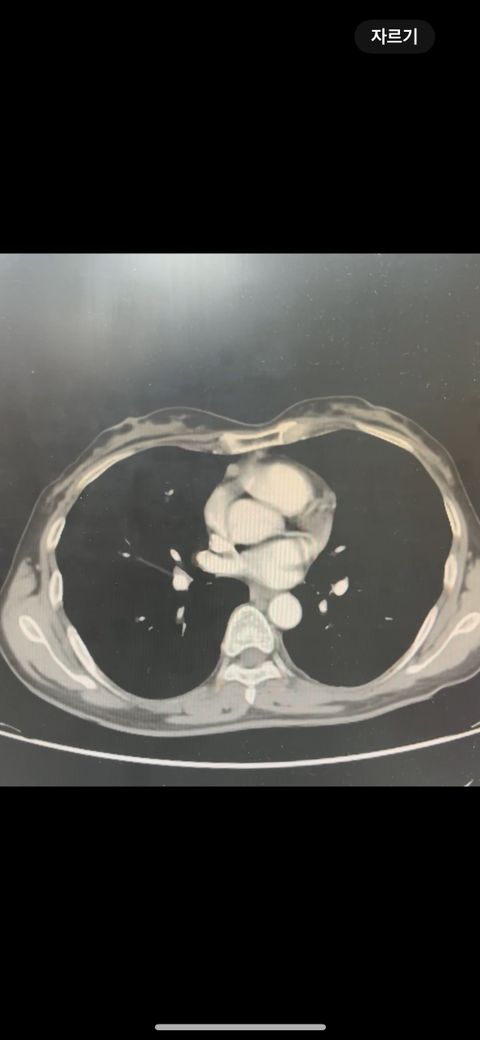

복부 ct 영상 판독부탁드립니다.!

결과는 3일 후 볼 예정인데 우선 영상만 받은 상태이고 너무 궁금한데 영상가지고 판독을 못해서요,,

이 사진가지고 확인할 수 있을까요 ?